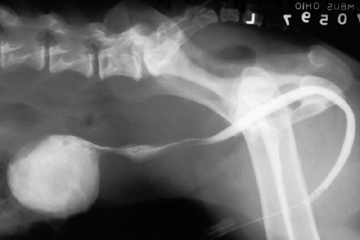

A positve contrast cystogram is performed by injecting contrast medium retrograde into the bladder. The procedure is the method of choice for identifying bladder location, tears or communication with adjacent structures.